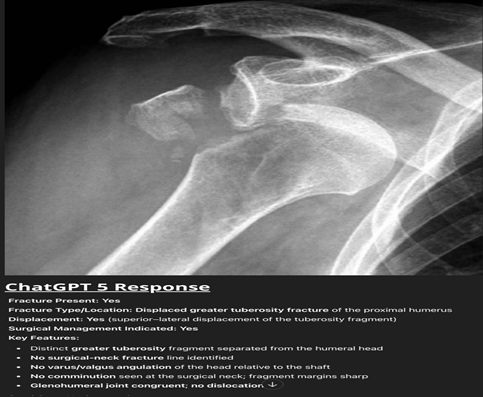

ChatGPT-5 demonstrated strong performance in detecting the presence of fractures, though with variability between anatomical sites. In the proximal humerus group (n = 60; 48 fractures, 12 normal), the model identified 42 of 48 fractures and correctly labeled all 12 normals, resulting in sensitivity 87.5%, specificity 100%, and κ = 0.74 (substantial agreement). False negatives were predominantly non-displaced or minimally displaced surgical neck fractures. For example, in a case with a fracture dislocation of the proximal humerus, ChatGPT-5 correctly identified a displaced GT fracture but failed to detect an associated anterior GH dislocation, despite clear humeral head displacement relative to the glenoid, highlighting its blind spot for associated dislocations critical for surgical planning (Fig. 1).

Figure 1: Anteroposterior shoulder radiograph of the shoulder showing a displaced fracture of the greater tuberosity with clear anterior glenohumeral dislocation. ChatGPT-5 correctly identified the fracture but failed to recognize the associated dislocation.